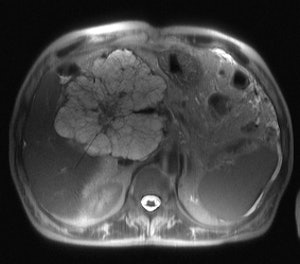

A case in point that determines management is whether pancreatic lesions are solid or cystic. A solid lesion must be resected, if possible, according to Bassi, while some cystic lesions can be followed up, as will be covered more fully by Zamboni, who will illustrate the different pathological patterns of pancreatic neoplasms, cystic and solid, their immunohistochemistry, and the possible progression from benign to malignant pancreatic tumor.

Of vital importance in pancreatic management is whether or not the tumor is locally advanced. Vessel wall infiltration will often contraindicate surgery, but it remains difficult to distinguish infiltration from neoplastic tissue or benign inflammatory or desmoplastic reaction, when there is contact between the tumor and the vessel. Delegates can learn about the pathological criteria for vessel wall infiltration and the pattern of perivessel infiltration from Dr. Giuseppe Zamboni, chair of the pathology department at Negrar Hospital, Verona, Italy. His presentation about the added value of the pathologist will cover the features of different pancreatic neoplasms, as well as the histopathological findings that enable tumor characterization and those that show prognostic relevance.